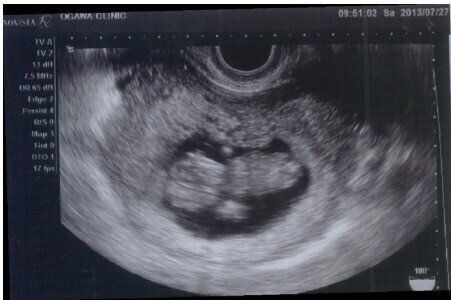

ママたちに人気!立体的で表情もわかる3D・4D 超音波

2Dの情報をコンピューターで再構築して着色し、立体的な画像として見せるのが3D。また、3D画像を動く画像として鮮明に見せるのが4Dです。

どちらも体の内部を見ることはできませんが、手足の指や顔の表情、しぐさなど、体の外表面的な画像をリアルに映し出します。